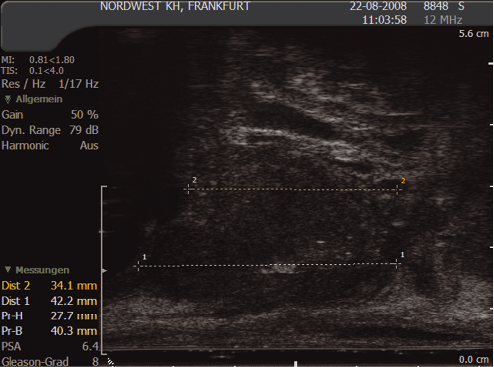

6.5 Prostate measurement

It is routine to measure the prostate volume (in g/ml)), which may be important in offering treatment options. The prostate is measured in three planes:

In the transverse view: anterior to posterior (width) (1) and height (2); and in the longitudinal plane from the bladder neck to the apex (length) (3). This can be calculated using the formula:

Ω/6 × height × width × length (in cm) (Ω/6 may be substituted by 0.51)

Most ultrasound machines will automatically calculate the volume.

Fig. 13. Prostate measurement – sagittal view

(Courtesy: S. Hieronymi)